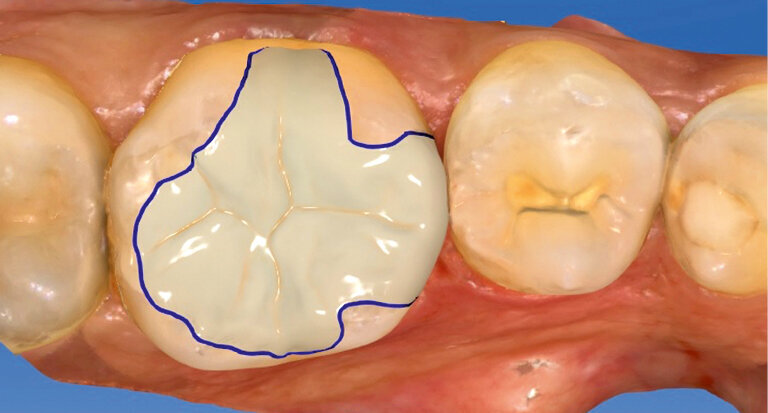

Fig. 3: Designing the inlay in the CAD module

Shade selection is performed on the natural dentition, primarily on the neighbouring teeth. We decided to use shade HT A2. The HT blocks are a good choice, particularly when it comes to producing fairly small restorations such as inlays as they provide a pronounced chameleon effect. Once the old amalgam was removed, the tooth was prepared in line with the recommended preparation guidelines (Fig. 2). Then, an optical impression was taken using an intraoral scanner and the inlay was designed in the CAD module (Fig. 3). Subsequently, the restoration was ground from the block.

In the present case, a try-in was performed immediately after the grinding process to check the fit of the inlay with the natural residual tooth structure (Fig. 4).